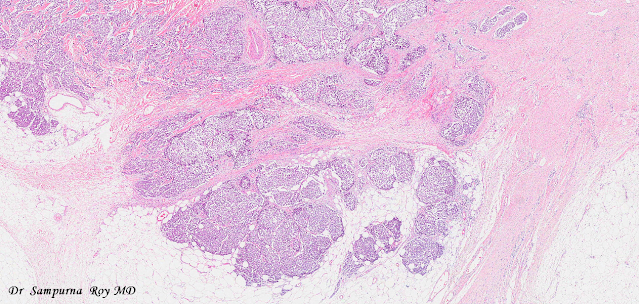

Dermatopathology Case 164

A 75 year old male.

Mass on right arm.

Immunohistochemistry- cytokeratin 20 (+), CAM5.2 (+), Neuron-specific enolase (+)